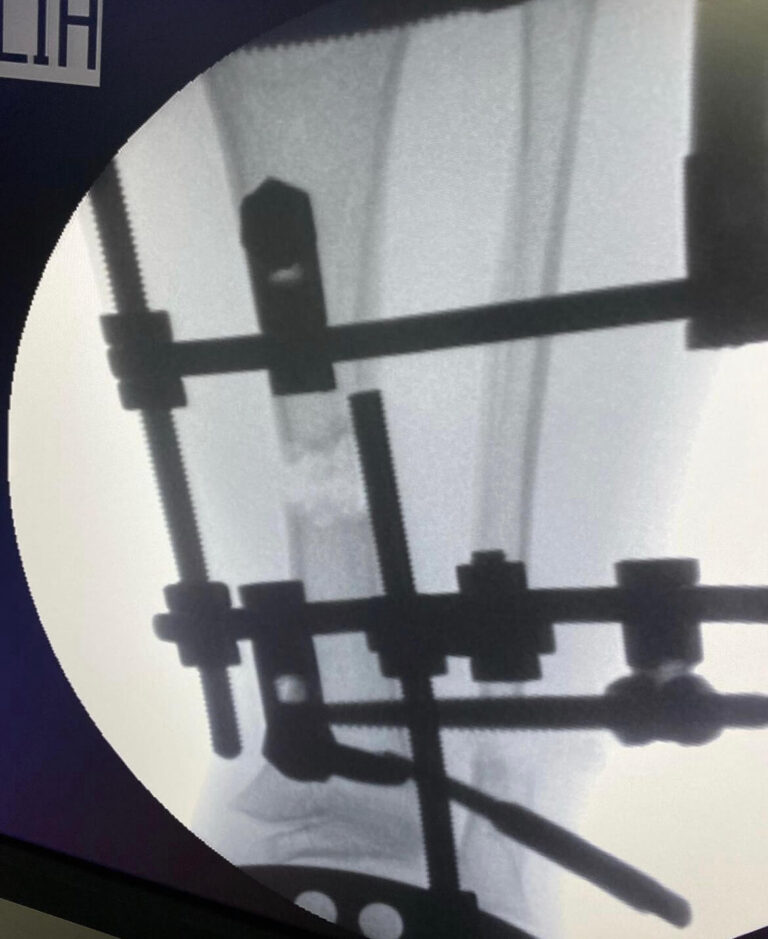

Современная сложная реконструктивная ортопедия в

мц «ЛАДИСТЕН КЛИНИК» город Киев Украина

- Малоинвазивные хирургические методы, позволяющие минимально вмешиваться в организм пациента и гарантируют эффективное лечение и легкую адаптацию.